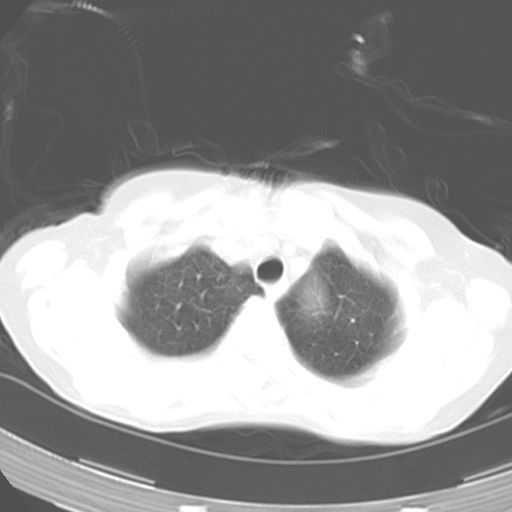

以下是引用dyqct在2006-12-7 21:08:00的发言:[br]考虑:1、肝内外胆管多发性结石伴肝左叶外侧段肝萎缩;[br] 2、右膈下多发脓肿;[br] 3、右侧少量胸腔积液、斜裂积液;[br] 4、左肾囊肿。

以下是引用jiazh在2006-12-7 20:37:00的发言:[br]肝脏周围半狐形低密度影,肝脏表面受压推移,考虑膈下脓肿可能性大;2、右侧胸腔积液

以下是引用拾荒者在2006-12-7 21:44:00的发言:[br]肝内外胆管多发结石,右膈下多发脓肿,右胸膜腔及叶间裂积液,左肾囊肿。[br] [br]